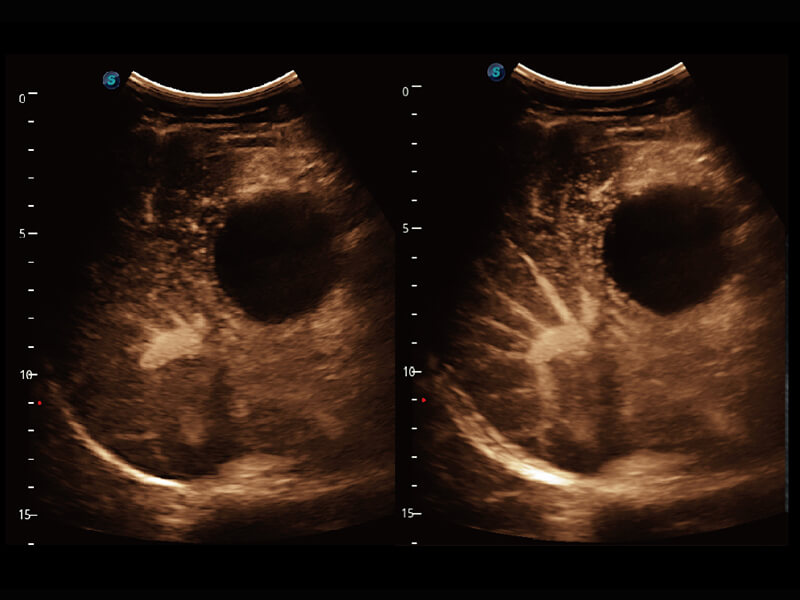

S60探头工艺,从前端信号处理每一个环节采集无损声学数据,真实还原组织原貌,再现解剖细节。

• 腹部单晶体探头( C1-6A )